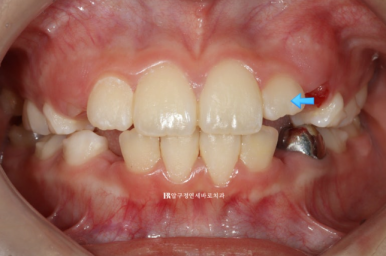

23.11.4

첫번째 세트가 거의 끝나갈때의 모습입니다.

화살표 치아가 장치와 맞지 않게 되어 적절한 시기에 재제작을 했습니다.

장치가 안 맞는다고 무조건 재제작이 아닙니다.

적절한 시기까지 착용하면서 주치의가 판단해서 재제작에 가장 유리한 시기에 재제작을 하는 것이 좋습니다.

전체 치료기간을 줄일 수 있습니다.